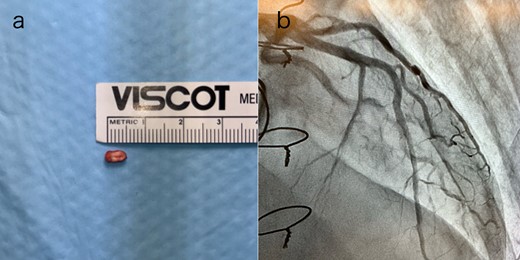

Postoperatively, an electrocardiogram revealed anterior ST-segment elevation, indicative of myocardial ischaemia. The patient then developed renal insufficiency. Given his haemodynamic stability, he was initially managed using coronary dilators and heparin. To improve renal function, coronary angiography was performed on the 10th postoperative day, which revealed a filling defect and 90% stenosis in the LAD artery (Fig. 1). Computed tomography (CT) revealed a high-density mass in the LAD artery with a mean CT value of 400 Hounsfield units (HUs) (Fig. 2). These findings indicated embolism, possibly due to a pledget from a previous surgery. A transcatheter approach was employed to remove the embolus, which was successfully extracted using a snare (Fig. 3a). Angiographic assessment revealed that the previously stenotic LAD demonstrated full perfusion, consistent with a thrombolysis in myocardial infarction (TIMI) flow grade of 3 (Fig. 3b). The patient recovered from catheterization without complications.

(a) The pledget was removed by transcatheter; (b) TIMI Grade 3 flow in the LAD artery after percutaneous coronary intervention.